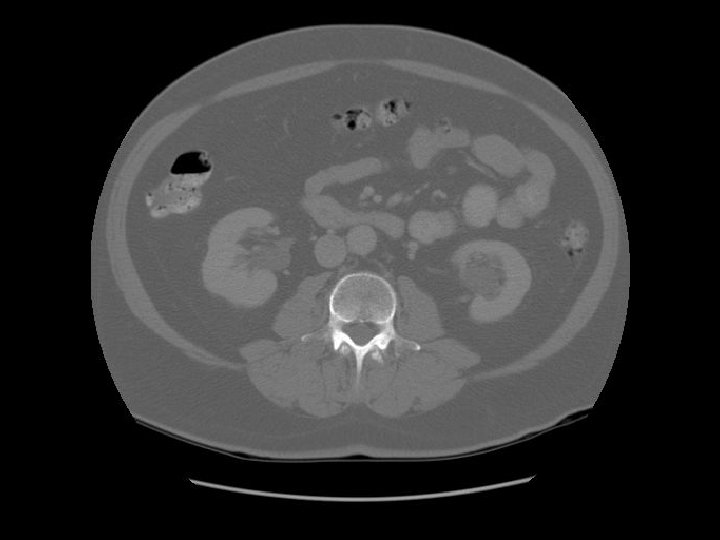

Pancreas Splenic vein The splenic vein lies in the posterior pancreatic grove and joins the superior mesenteric vein to form the portal vein.

Pancreas Duodenal bulb IVC Rt renal artery The right renal artery is retrocaval.

Small cyst in the left kidney.

Lt renal vein IVC Left renal vein emptying into the IVC.

Transverse colon Ileum

Kidney Right Kidney